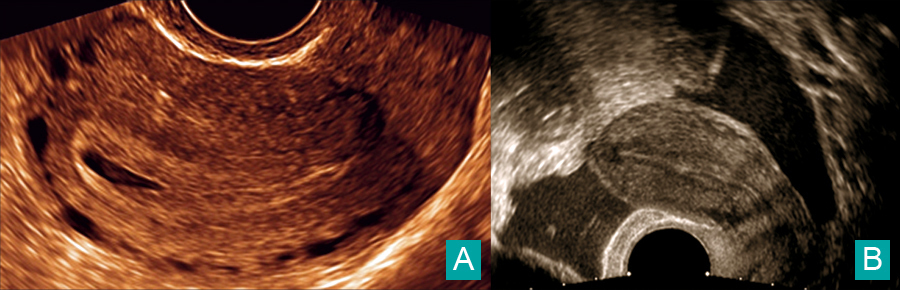

Charlotte Laplane, Claude d’Ercole (La Revue du Praticien) A. Pseudo-sac gestationnel.B. Épanchement du cul-de-sac de Douglas.